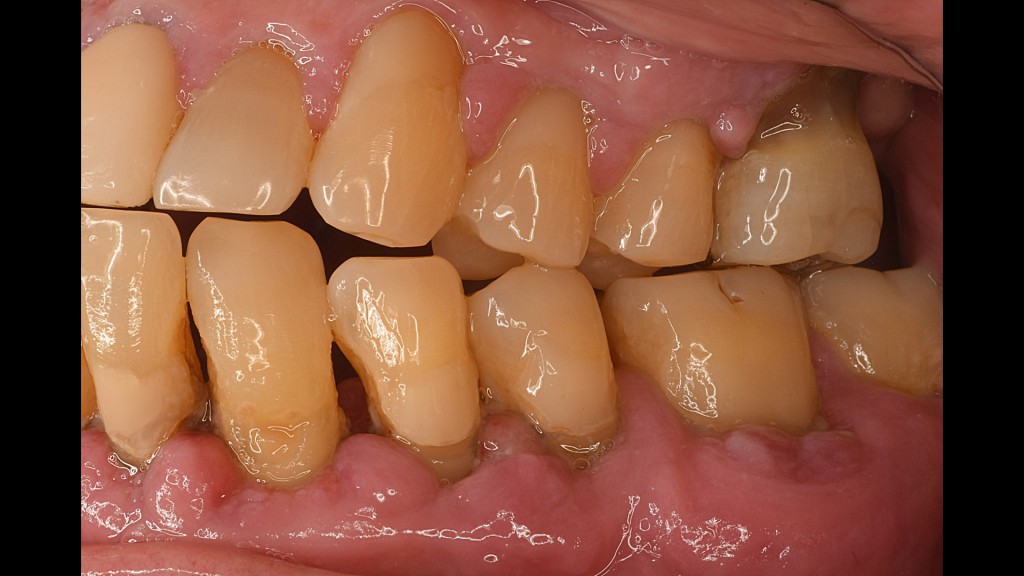

Ⅲ期 中等度歯周炎

歯周ポケット5mm以上〜7mm以内

炎症が奥まで進み、歯茎はブヨブヨした状態になり、血や膿が出て、口臭もひどくなる。

歯槽骨がかなり溶けて、歯がぐらついてくる。